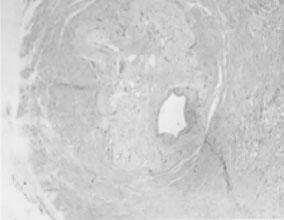

图5—4 肾动脉肌纤维结构不良

在国外青年人肾动脉狭窄大多数是由于纤维肌性发育异常引起的(见图5—4)。根据动脉壁发育异常最明确的部位分为内膜、中层和动脉周围(外膜)的纤维性发育异常。中层病变进一步分为中层纤维组织增生(约占70%),中层周围组织纤维增生(约占20%)和中层增生(中层增生与内膜增生约占5%)。这些病变易导致中层组织分离并可能造成动脉瘤及动静脉瘘。